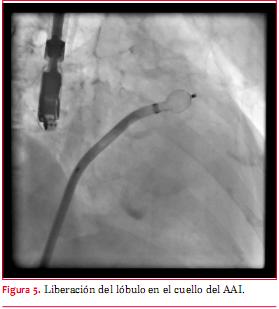

Se seleccionó para ambos casos un dispositivo Amplatzer Cardiac Plug® de 24 mm en función de los diámetros del lóbulo y disco del dispositivo de acuerdo a las medidas obtenidas de cuello y boca. Se utilizó una vaina de 13 Fr tranvenosa cuyo extremo distal se ubicó en el cuello del AAI como instrumento para avanzar el dispositivo de cierre, con especial precaución para prevenir la embolia aérea. Posteriormente, se avanzó el dispositivo hacia el extremo distal de la vaina, liberando primero el lóbulo y luego el disco. Se aseguró que estos se ubicaran en una posición perpendicular con respecto al eje largo del AAI. Se comprobó además la completa expansión y el correcto anclaje del dispositivo (figuras 5 y 6).